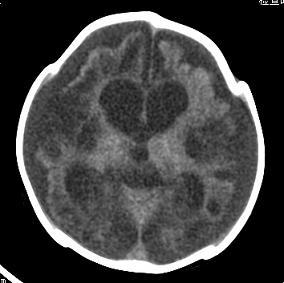

男,4个月大,2个月前无诱因下四肢抽搐、伴呕吐,近2天来抽搐频发,伴发热。查体:双眼疑视,神萎、纳差;颈抵抗,四肢张力高。

病史太长了,原因不好定,不过如果2个月前小儿正常的话可考虑积水型无脑畸形,积水型无脑畸形小儿刚生下来表现可正常,存活一两个月后出现症状.

另不除外缺血缺氧性脑病,感染等改变

2个月前缺血缺氧性脑病留下的后遗症。

脑出血后,软化灶形成了。脑发育不良

支持缺血缺氧性脑病留下的后遗改变(脑软化灶+脑发育不全+双侧慢性硬膜下积液+小头畸形)。

要注意化脓性脑膜、脑炎,硬膜下积脓,脑积水的可能,建议腰穿助诊。